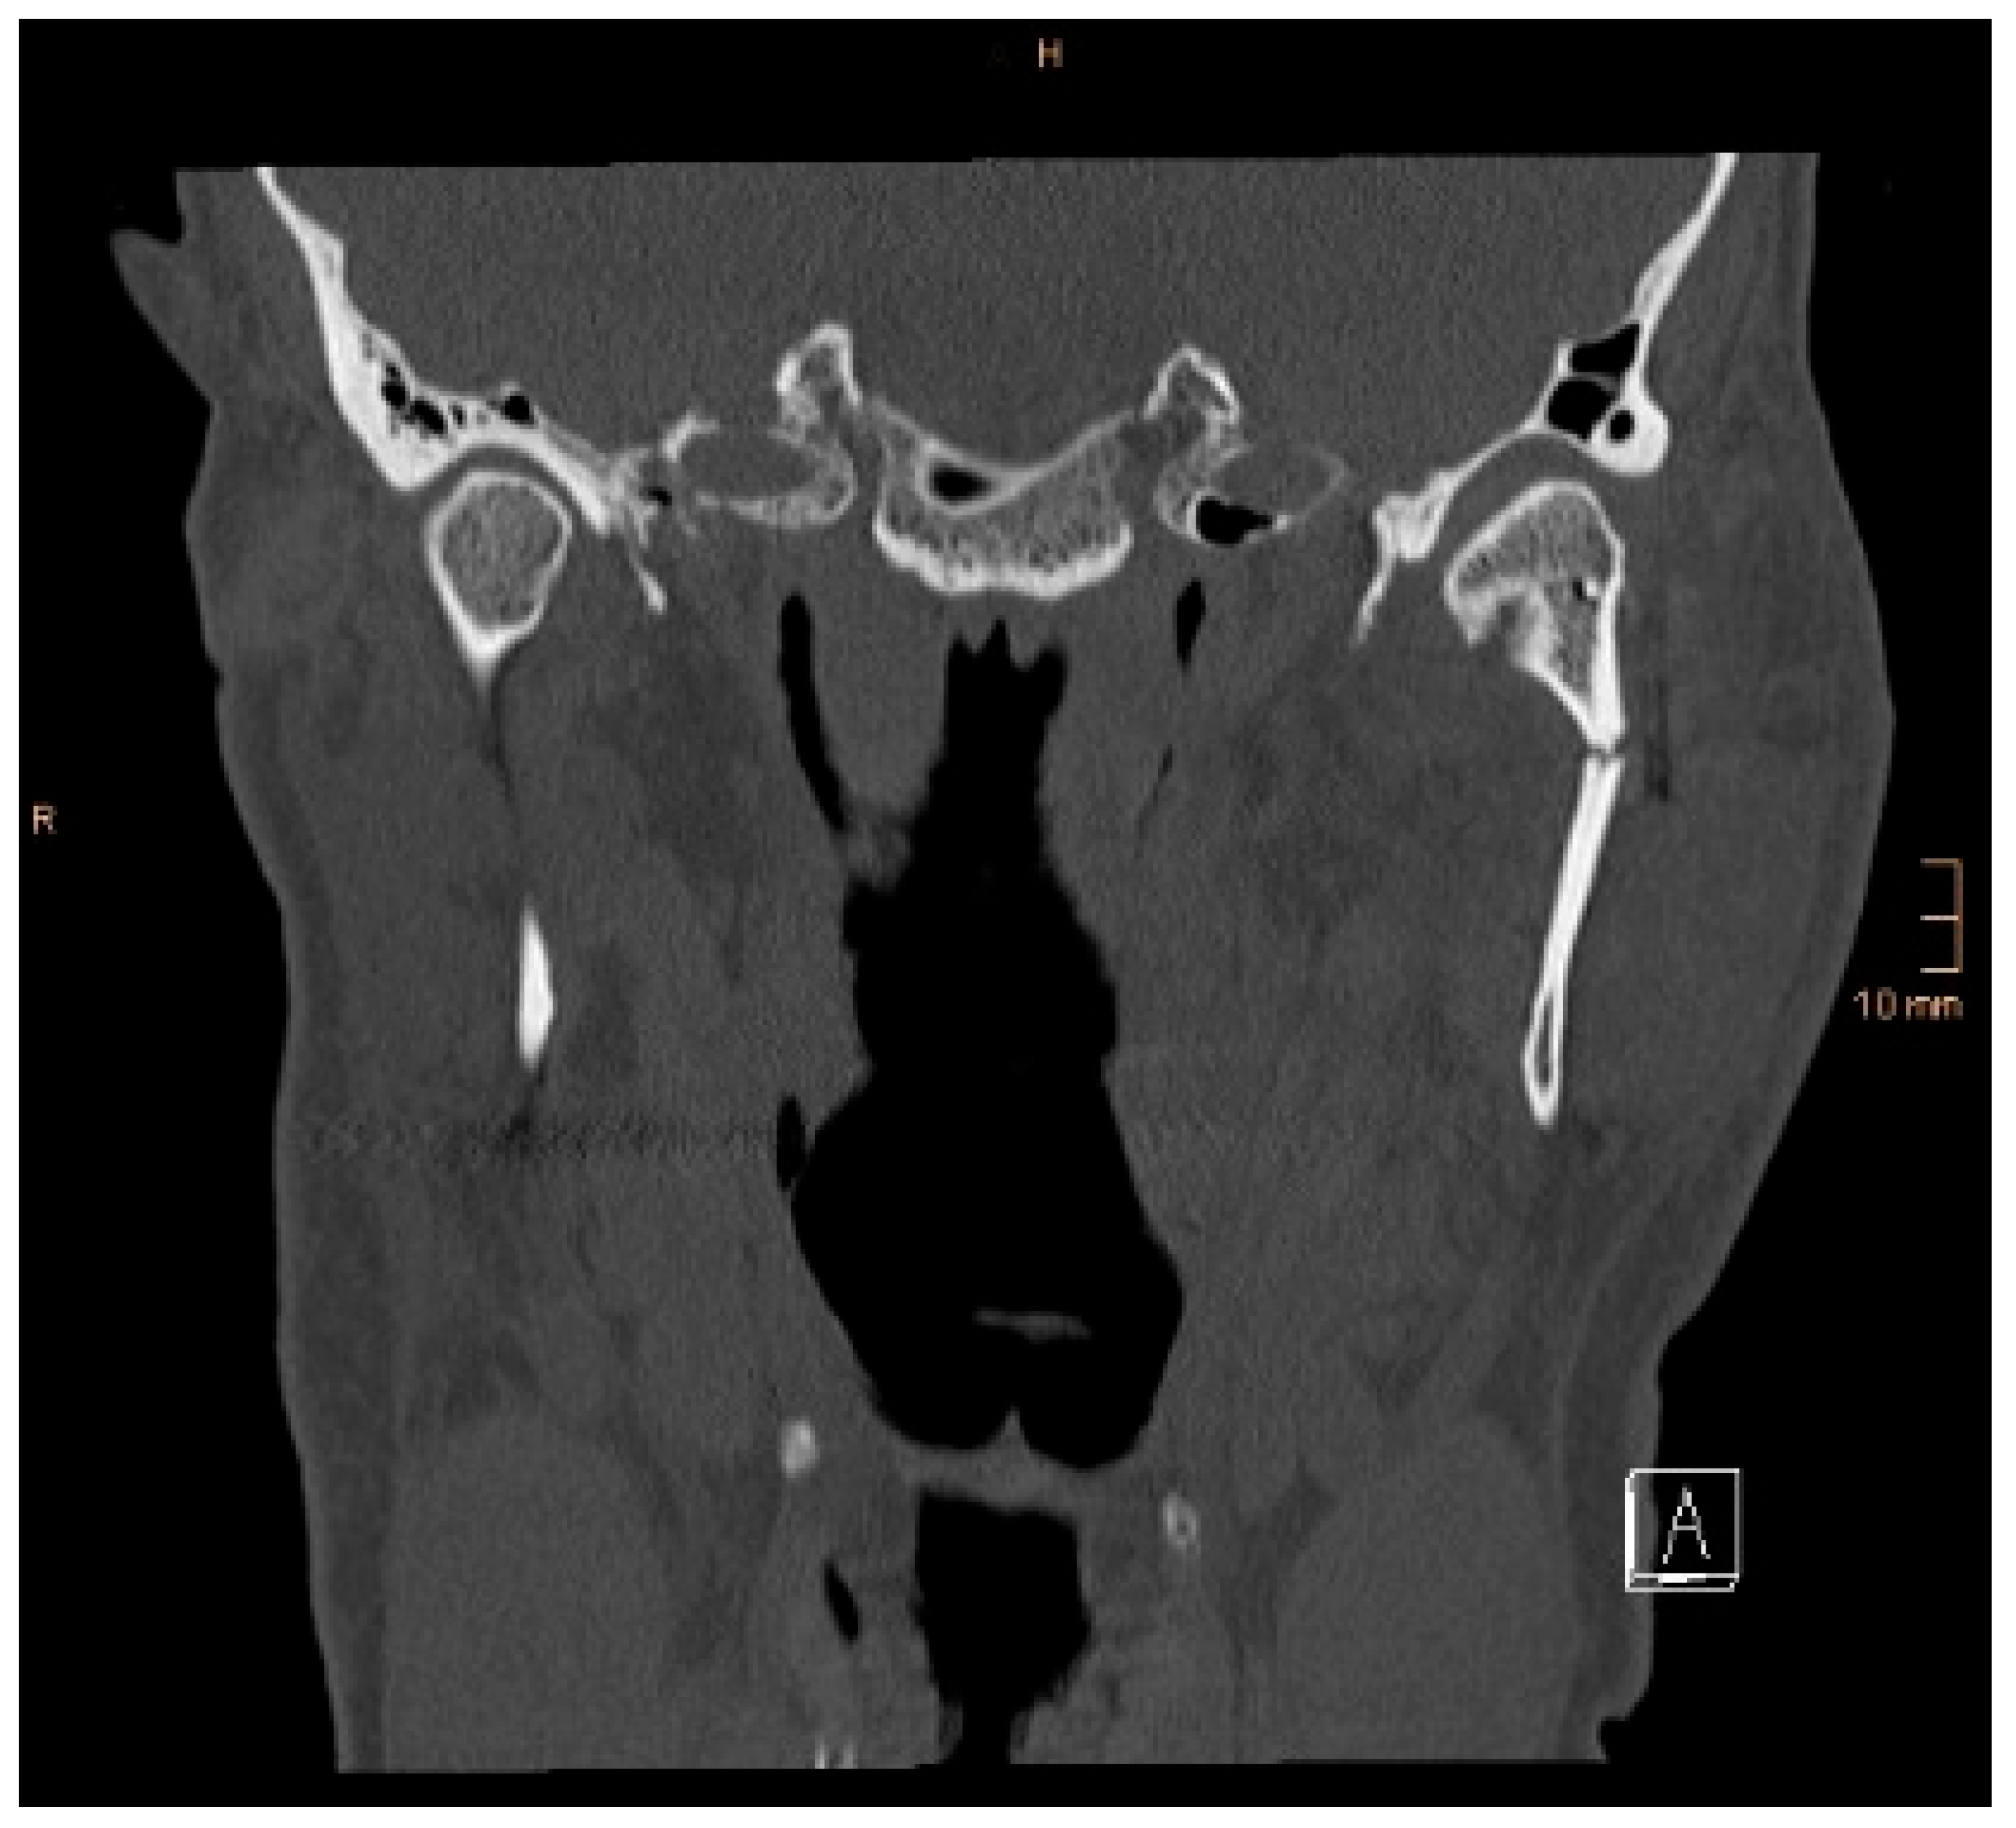

Figure 5. Coronal CT scan showing both condyles after ORIF. A widening of the mandible, caused by a small lingual gap that persisted even after lag screw osteosynthesis at the symphysis, resulted in an angulation of the condylar neck on the right-hand side (same patient as in Figure 3 and Figure 4). The image shown was taken on the third postoperative day after drainage removal and the situation did not worsen over time (last follow-up 1 year postop).

Two operations had to be redone because of inadequate reposition in the symphysis/parasymphysis with broad (>2 mm) lingual splay. In both cases, straight miniplates were removed. Osteosynthesis was achieved with lag screws. Figure 3 depicts plate osteosynthesis of a symphyseal fracture with a broad lingual gap (Figure 3). Figure 4 shows the same patient after redo operation and osteosynthesis of the same fracture with a lag-screw and a marked reduction in the lingual splaying (Figure 4). Figure 5 demonstrates the condylar reduction in the frontal plane in the same patient. Figure 6 and Figure 7 show the patient’s occlusion (Figure 5, Figure 6 and Figure 7). The third redo operation was due to nonunion and infection of an angular fracture with fracture of the two condylar plates. In this case, after removal of the infected miniplate, the angle fracture was stabilized with a reconstruction plate and a miniplate from an extraoral approach; the two broken miniplates at the condylar process were left in situ.

Figure 4. Axial CT scan showing the same patient as in Figure 3 after replacing the miniplates with a lag screw and considerable closure of the lingual gap. However, a small gap in the lingual cortical bone remained, and possibly determined a widening of the mandible.